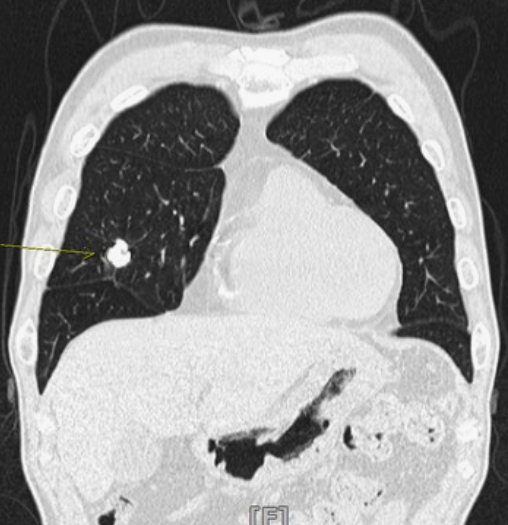

2️⃣ 저선량 흉부CT

최근엔 저선량 CT 검사로 조기 발견율이 높아졌습니다.